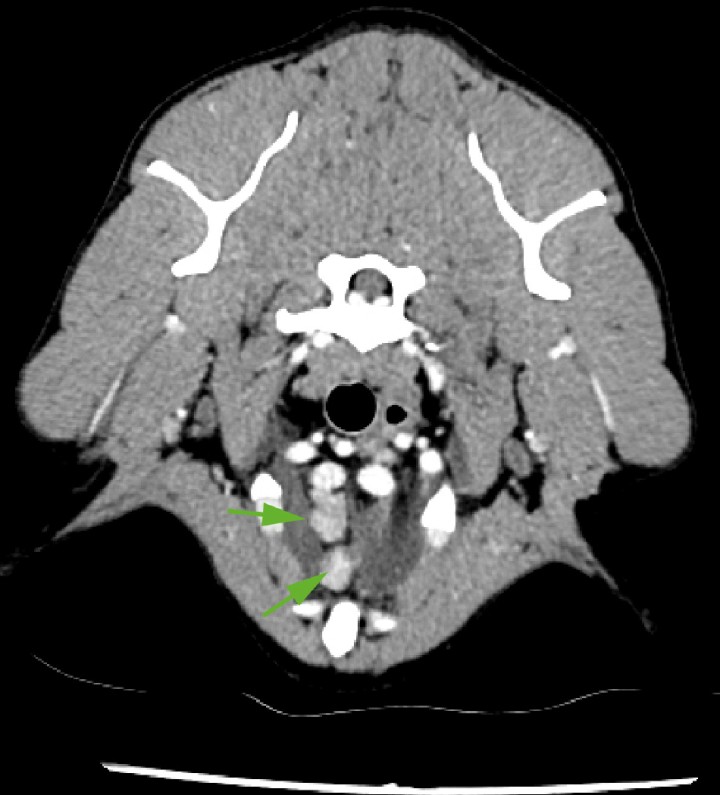

<p>Imagen de TC en ventana tejido blando postcontraste de corte trasversal; a la entrada del tórax, se evidencian los linfonodos mediastínicos craneales y esternal (flechas) aumentados de tamaño, con márgenes bien definidos, parénquima homogéneo, atenuación (50 UH) en fase precontraste y captación de contraste homogénea y moderada. Se aprecia, además, ligera hiperintensidad de la grasa perinodal.</p>

Imagen de TC en ventana tejido blando postcontraste de corte trasversal; a la entrada del tórax, se evidencian los linfonodos mediastínicos craneales y esternal (flechas) aumentados de tamaño, con márgenes bien definidos, parénquima homogéneo, atenuación (50 UH) en fase precontraste y captación de contraste homogénea y moderada. Se aprecia, además, ligera hiperintensidad de la grasa perinodal.